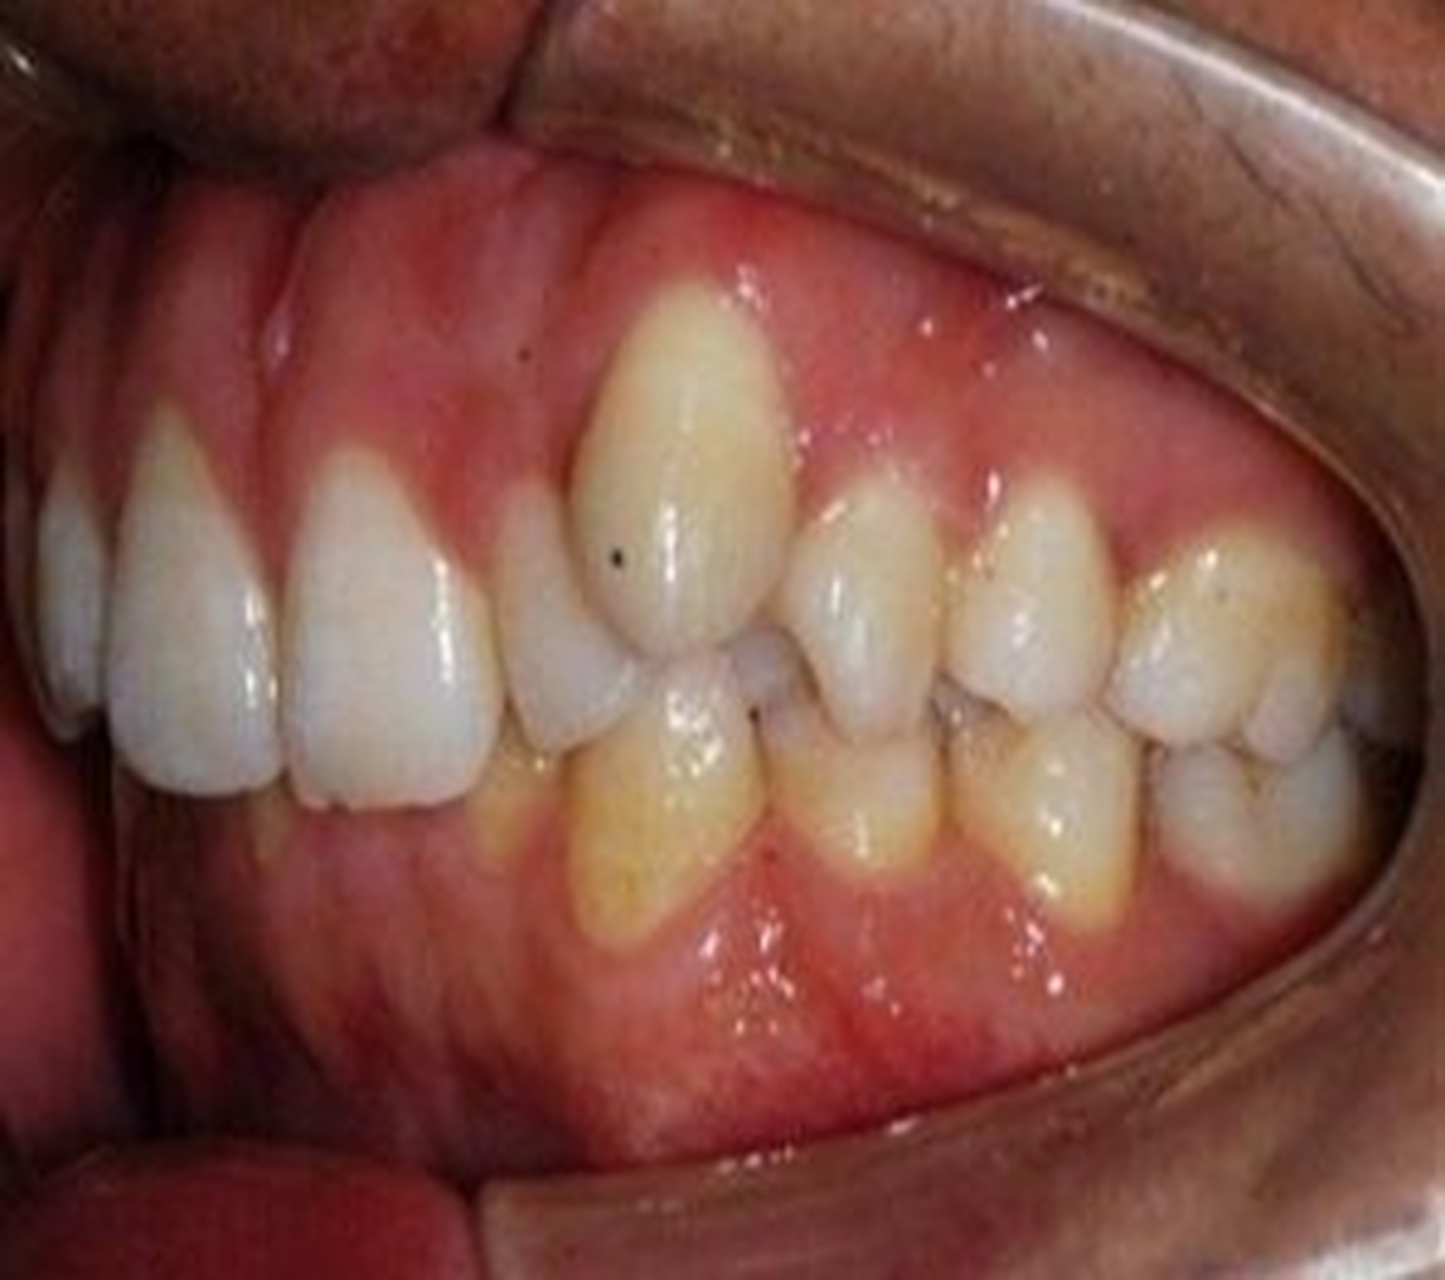

6岁娃长出双排牙,医生提醒:有这些习惯赶紧改_孩子_牙齿_乳牙

深圳种植牙96缺牙时间长对颌牙伸长了怎么办?